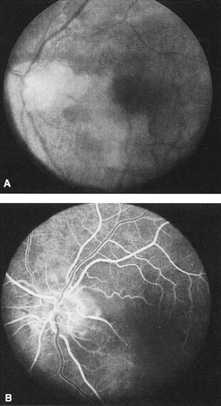

Cilioretinal arteries can be selectively obstructed (Fig. 3). More commonly, however, they occur in association with central retinal vein obstruction.113 When they supply a significant portion of the macula, decreased visual acuity is common. Prognosis for visual outcome in such patients is good. Brown and co-workers114 studied 10 eyes having an isolated cilioretinal artery obstruction. Of those, 60% had an initial visual acuity of 20/40 or better and on follow-up examination, all eyes but one had a best-corrected visual acuity of 20/40 or better.114

Fig. 3. A: Cilioretinal artery obstruction showing opacity of the retina in the area of obstruction. B: The cilioretinal artery has begun to fill after the branches of the central retinal artery but is still not completely filled at this point in the angiogram.